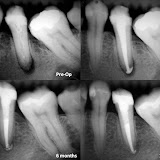

Proservacao de 18 meses - retratamentos